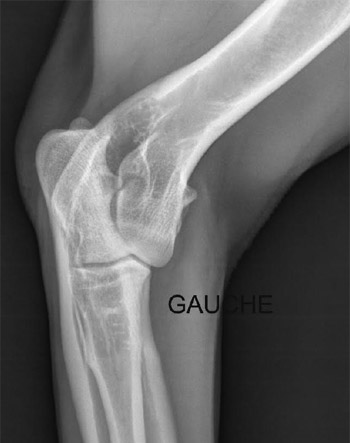

La dysplasie des coudes (ED)

La dysplasie du coude est connue chez de nombreuses races de chiens. Elle touche principalement les chiens de grande race à croissance rapide.

Le terme de dysplasie du coude est apparu en 1993. Il désignait initialement une arthrose généralisée du coude, associée à une non-union du processus anconé. D'autres affections se sont ensuite ajoutées : fragmentation du processus coronoïde médial, ostéochondrite disséquante ou incongruence articulaire.

Une origine génétique a été démontrée, avec une participation importante de l'environnement.

Les diagnostics sont classés selon les stades suivants :

- Stade 0 (normal)

- Stade SL (stade limite)

- Stade 1 (acceptable)

- Stade 2 (moyen)

La lecture des radios stade 0, SL ou 1 est obligatoire pour obtenir les cotations 4, 5 ou 6 et pour l'homologation des Titres de Champions de France.

Seuls les stades 0, SL et 1 obtiennent le Label ED.